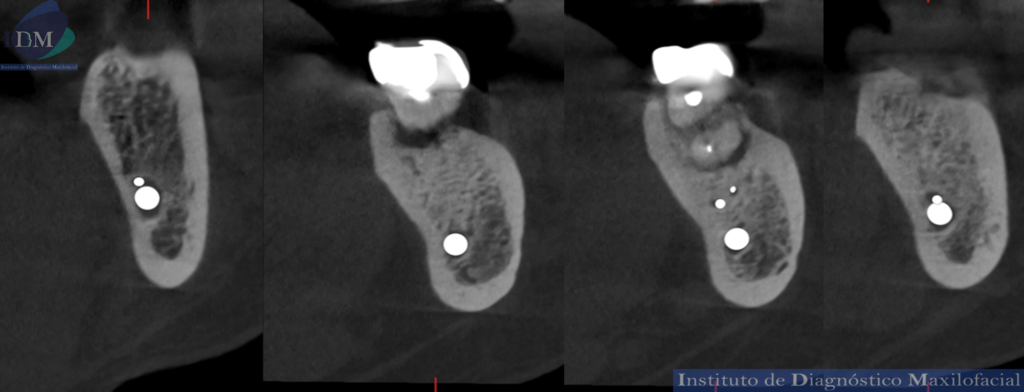

Así mismo se evidencia en la tomografía localizada una variante anatómica por parte del conducto dentario inferior. Donde se visualizada dos ramos accesorios del tronco principal sin confluencia.

CORTES CORONALES